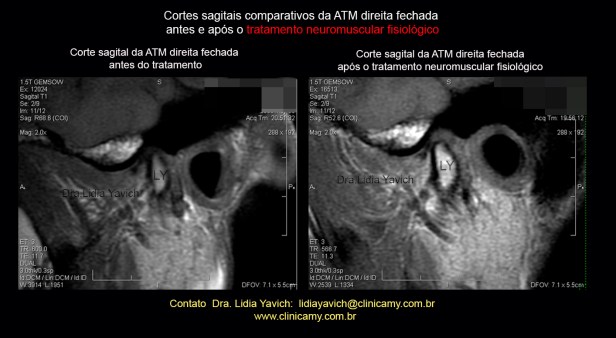

RNM: cortes sagitais comparativos da ATM esquerda, boca fechada, antes e após o tratamento Neuromuscular Fisiológico.

RNM: cortes sagitais comparativos da ATM esquerda, boca fechada, antes e após o tratamento Neuromuscular Fisiológico.

Nota-se a descompressão tridimensional da articulação. Objetivo primordial neste caso específico.

RNM: cortes sagitais comparativos da ATM esquerda, boca fechada, antes e após o tratamento Neuromuscular Fisiológico.

RNM: cortes sagitais comparativos da ATM esquerda, boca fechada, antes e após o tratamento Neuromuscular Fisiológico.

Nota-se a descompressão tridimensional da articulação. Objetivo primordial neste caso específico.

RNM: cortes sagitais comparativos da ATM esquerda, boca fechada, antes e após o tratamento Neuromuscular Fisiológico.

RNM: cortes sagitais comparativos da ATM esquerda, boca fechada, antes e após o tratamento Neuromuscular Fisiológico.

Nota-se a descompressão tridimensional da articulação. Objetivo primordial neste caso específico.

RNM: cortes sagitais comparativos da ATM esquerda, boca fechada, antes e após o tratamento Neuromuscular Fisiológico.

RNM: cortes sagitais comparativos da ATM esquerda, boca fechada, antes e após o tratamento Neuromuscular Fisiológico.

Nota-se a descompressão tridimensional da articulação. Objetivo primordial neste caso específico.